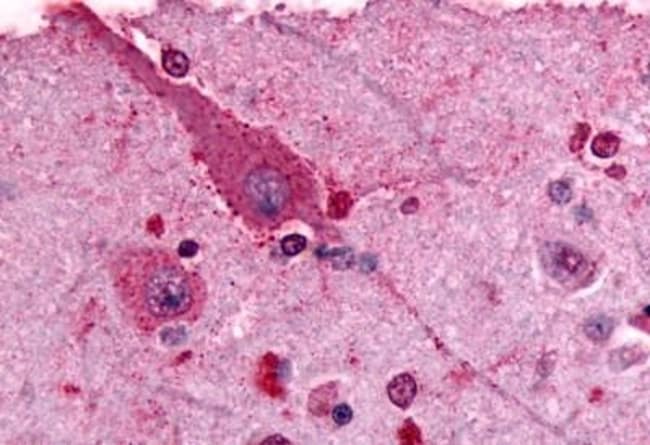

Invitrogen™ mGluR2 Polyclonal Antibody

Glutamate is the main excitatory neurotransmitter in the brain. For many years it had been considered to act only on the ligand-gated receptor channels-termed NMDA, AMPA and kainite receptors that are involved in the fast excitatory synaptic transmission. Recently, glutamate has been shown to regulate enzymes producing second messengers via specific receptors coupled to G-proteins. These receptors are called metabotropic glutamate receptors. In expression systems, Group-I receptors stimulate phospholipase C as revealed by an increase in phosphoinositide turnover and calcium release from internal stores. Group-II and -III receptors are coupled to the inhibition of adenylyl cyclase. The Group-I receptors include mGluR1a and mGluR5. The Group-II receptors in include mGluR2 and mGluR3.

| Immunohistochemistry (Paraffin), Western Blot | |

| Synthetic 17 amino acid peptide from N-terminal extracellular domain of human GRM2 / MGLUR2. | |